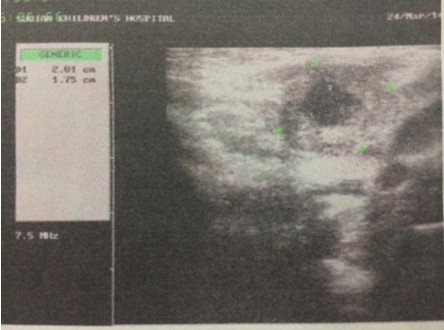

4个月大的婴儿,右颈部耳垂下方(2公分左右)有个硬疙瘩,婴儿无明显异常,吃奶睡觉等等一切正常,精神 状态很好,挂了3天的消炎水,图片为在2家医院做的B超,求解这个疙瘩是什么,需要怎么样治疗。医生叫继续挂消炎水进一步观察!(备注:B超2描述是:右侧颈部肌层后方探及22*15mm不均质低回声包块,其周围可见数枚低回声结节。 超声印象:右颈部包块伴周围淋巴结肿大。) 点击展开 匿名用户 2014-03-24 19:47 为您推荐: 其他回答 病情分析: 这个情况考虑是属于增生的症状, 指导意见: 你好,目前这个问题我建议及时消炎治疗,继续观察吧。 白其雨_6xwx 2014-03-24 21:36 相关问题 大夫您好我脖子右侧耳垂下方6公分左右 十五个月的宝宝耳垂前边脸颊上长了个长了个小疙瘩是怎么回事 十五个月的宝宝耳垂前边脸颊上长了个长了个小疙瘩是怎么回事

状态很好,挂了3天的消炎水,图片为在2家医院做的B超,求解这个疙瘩是什么,需要怎么样治疗。医生叫继续挂消炎水进一步观察!(备注:B超2描述是:右侧颈部肌层后方探及22*15mm不均质低回声包块,其周围可见数枚低回声结节。 超声印象:右颈部包块伴周围淋巴结肿大。)